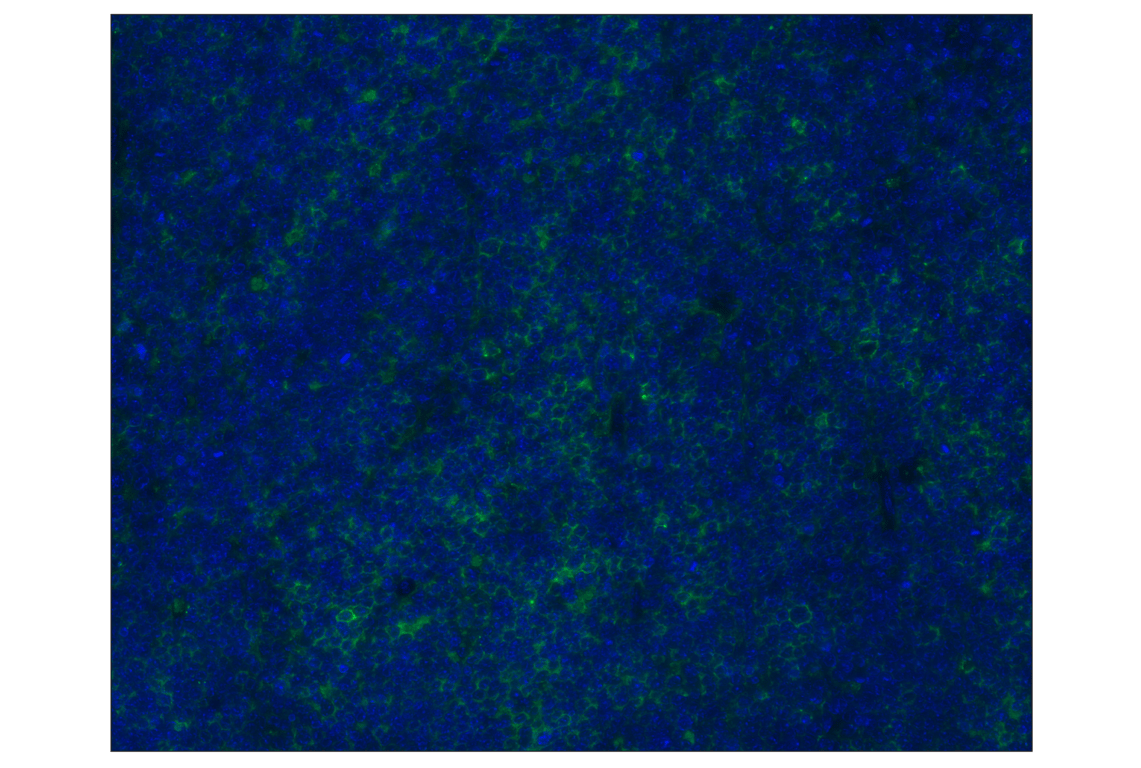

PD-L1 (D5V3B) Rabbit mAb (Alexa Fluor® 488 Conjugate) #20490

This Cell Signaling Technology® antibody is conjugated to Alexa Fluor® 488 fluorescent dye under optimal conditions. This antibody conjugate is expected to exhibit the same species cross-reactivity as the unconjugated PD-L1 (D5V3B) Rabbit mAb #64988.

PD-L1 (D5V3B) Rabbit mAb (Alexa Fluor® 488 Conjugate) recognizes endogenous levels of total mouse PD-L1 protein. Non-specific staining of keratinized epithelium has been observed.

Mouse

Monoclonal antibody is produced by immunizing animals with a synthetic peptide corresponding to residues surrounding Gly216 of mouse PD-L1 protein.